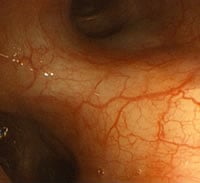

従来の内視鏡検査では、スペクトル幅の広い通常光を粘膜表面に照らしますが、通常光は診断に重要な粘膜表層の血管や微細模様などのコントラストを低下させるという原因となっていました。NBIは、特殊光によって粘膜の微小な血管や腫瘍の模様を強調してより詳しく観察し、小さな病変でも見落とさず発見することが可能となるシステムです。粘膜表層の毛細血管やわずかな粘膜の凸凹、深部血管などを協調して映し出すことのできるスペクトル幅の狭い光を照射することによって、微細な病変も確認しやすくなります。それによりごく初期段階でのがんの発見や、特殊光によって粘膜の微小な血管や腫瘍の模様を強調してより詳しく観察し、小さな病変でも見落とさず発見する検査に伴う患者さんの負担軽減が期待できます。

NBI画像